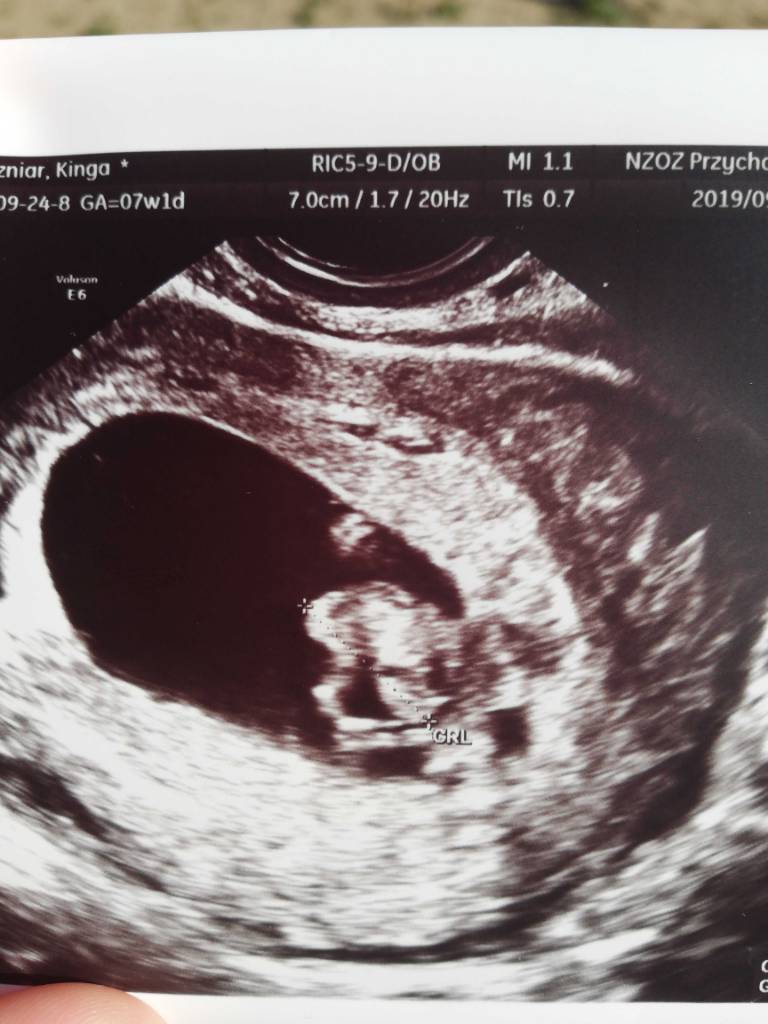

Jestem po :)

Wszystko w porządku. Ciąża potwierdzona. Według usg 4dni starsza niż on om :)

Karta ciąży założona. Kolejna wizyta 26.10

1569320036446.jpeg